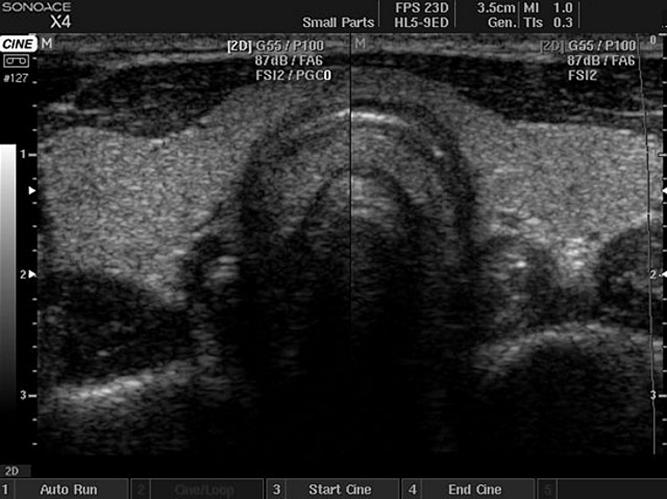

Лазерная вапоризация аденомы простаты в ЦКБ РАН, это удаление разросшейся ткани путем выпаривания. Выполняется эндоскопически. Это эндоурологическая операция, которая предусматривает проведение инструмента через мочеиспускательный канал т.е. без разрезов. Операция проводиться под контролем глаза. Это значит, что хирург видит зону выпаривания на экране монитора.

Лазерная вапоризация аденомы простаты — это выпаривание аденомы предстательной железы при помощи лазера. Операция проходит без разрезов. Через мочеиспускательный канал проводится лазерный световод и происходит выпаривание аденоматозной ткани. При проведении лазерной вапоризации аденомы простаты удаляются абсолютно любые размеры аденомы, ограничений по обьему нет!